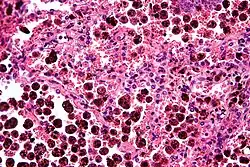

Comparison of pigmented pulmonary macrophages

| Disease | Macrophage name | Macrophage pigment appearance (HE stain) | Usual macrophage location | Associated medical history | Image | Image comment |

|---|---|---|---|---|---|---|

| Anthracosis | Black-brown granules | Interstitium (perivascular) |

|

Black arrow shows interstitial anthracotic pigment. Nearby macrophages (white arrow) can be presumed to contain anthracotic pigment. | ||